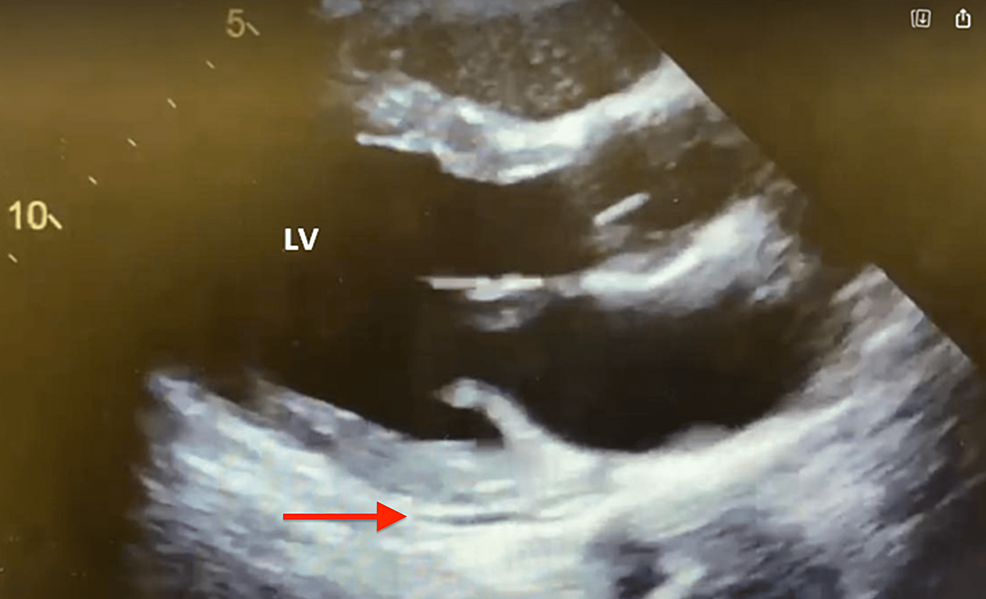

- 心エコー図:音波を使用して心臓の画像を作成します。心エコー図では、臓器のサイズ、形状、機能、心膜内の過剰な体液を確認できます。